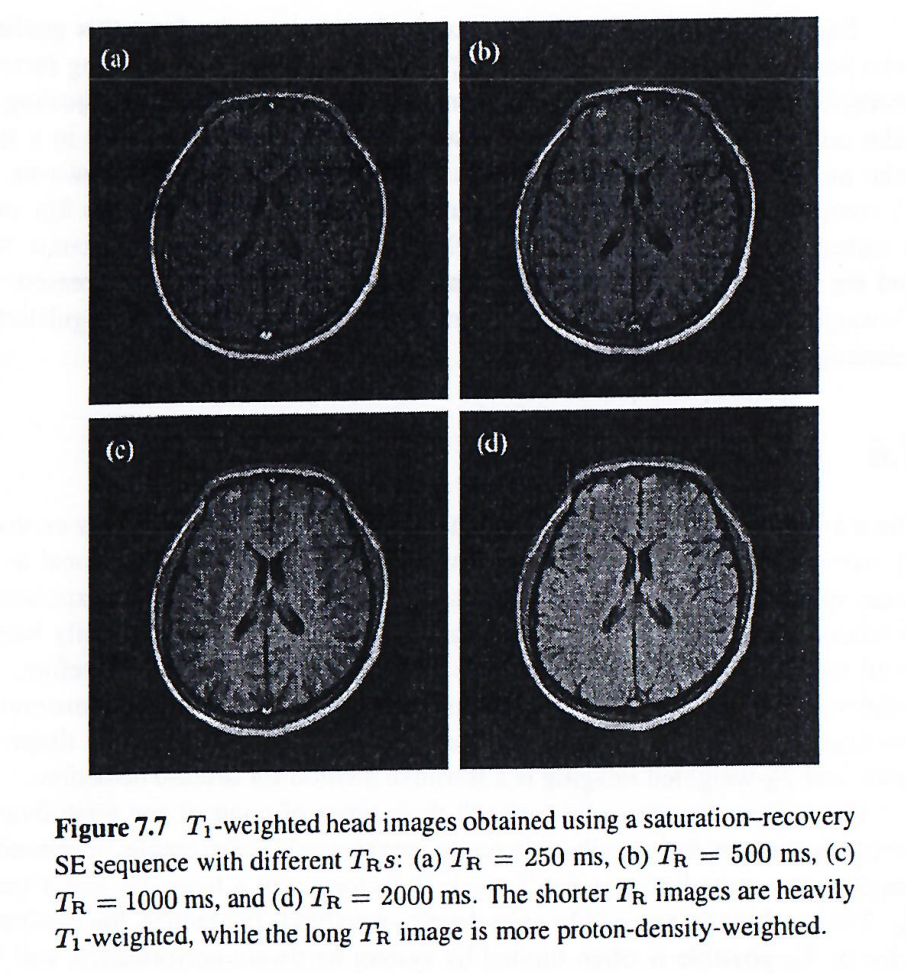

为了说明作为数据采集参数函数的组织对比度概念,下面两图使用具有不同T1T_1T1和T2T_2T2加权的饱和恢复自旋回波序列采集的。